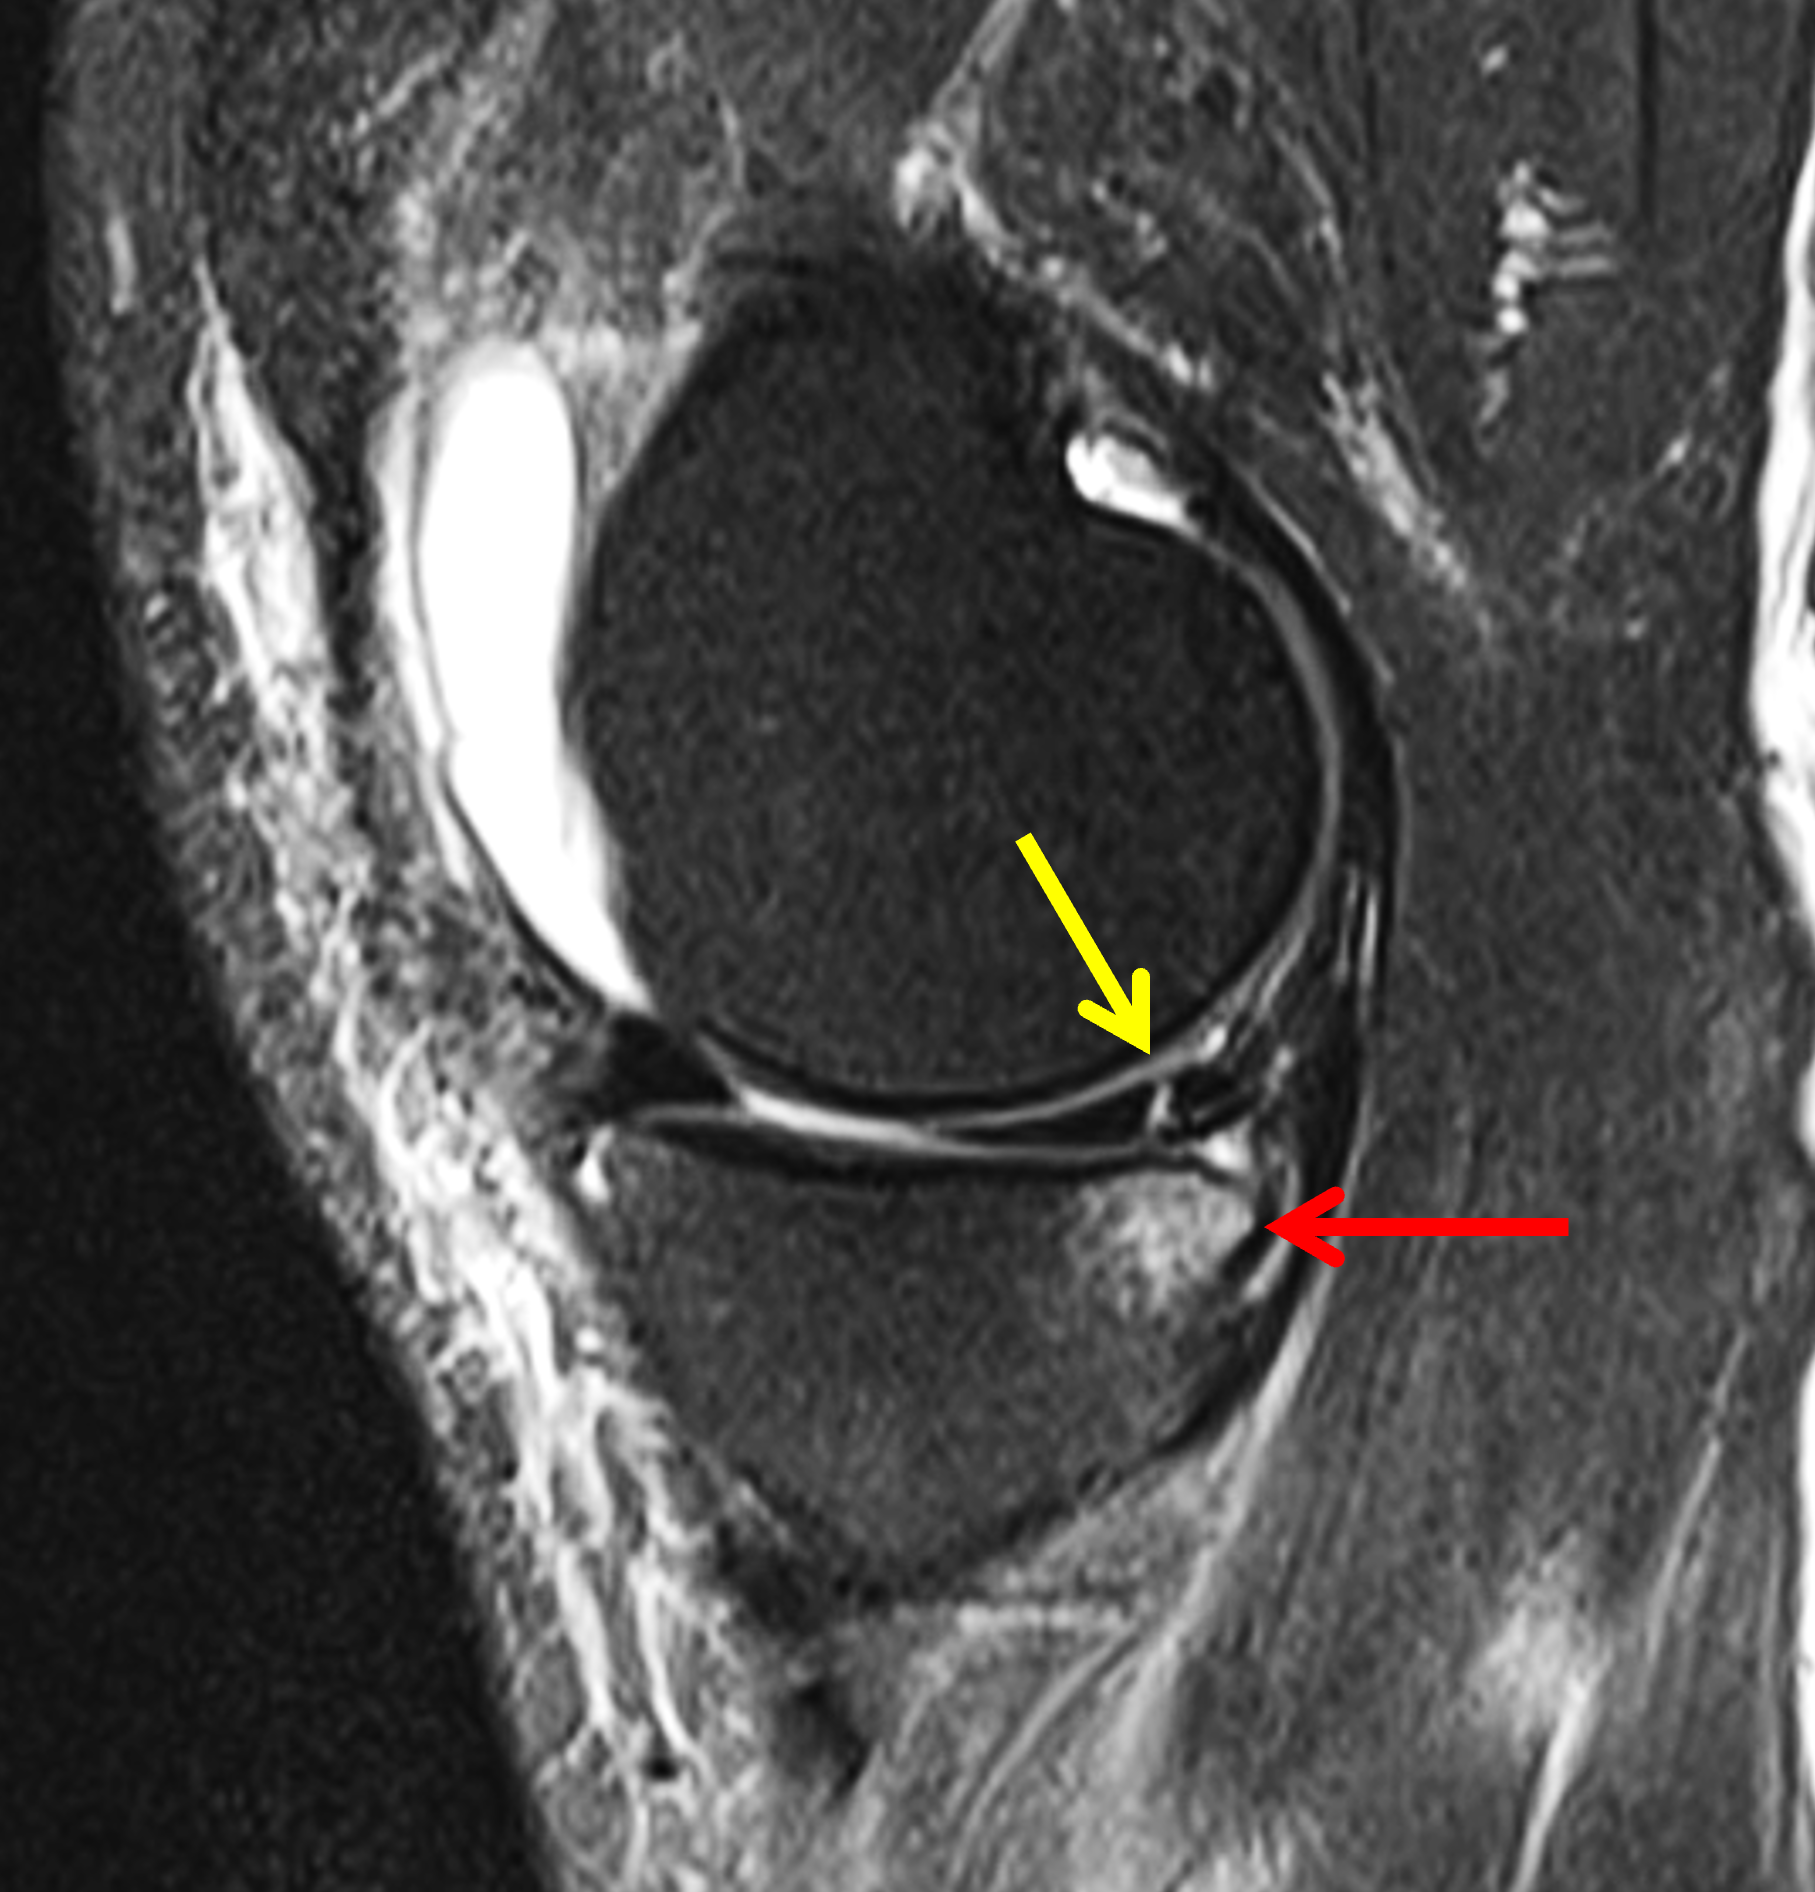

A 19-year-old collegiate baseball player sustained a twisting injury to the knee 3 weeks earlier. Sagittal (1A) proton density-weighted fat-suppressed image through the intercondylar notch, (1B and 1C) proton density-weighted images through the medial compartment, and (1D) fat-suppressed proton density image through the medial compartment are provided. What are the findings? What is your diagnosis?

Figure 2: (2A) Sagittal image through the intercondylar notch shows a complete tear of the anterior cruciate ligament (arrowheads). (2B and 2C) Near the posterior meniscocapsular junction of the medial meniscus, there is disruption of the posterior meniscotibial ligament (red arrow) and irregularity of the posterior meniscocapsular ligament (yellow arrow). (2D) On the fluid-sensitive sequence, linear high signal intensity is interposed between the ligaments and the posterior horn of the medial meniscus (arrowheads).

Anterior cruciate ligament tear with a medial meniscal ramp lesion.